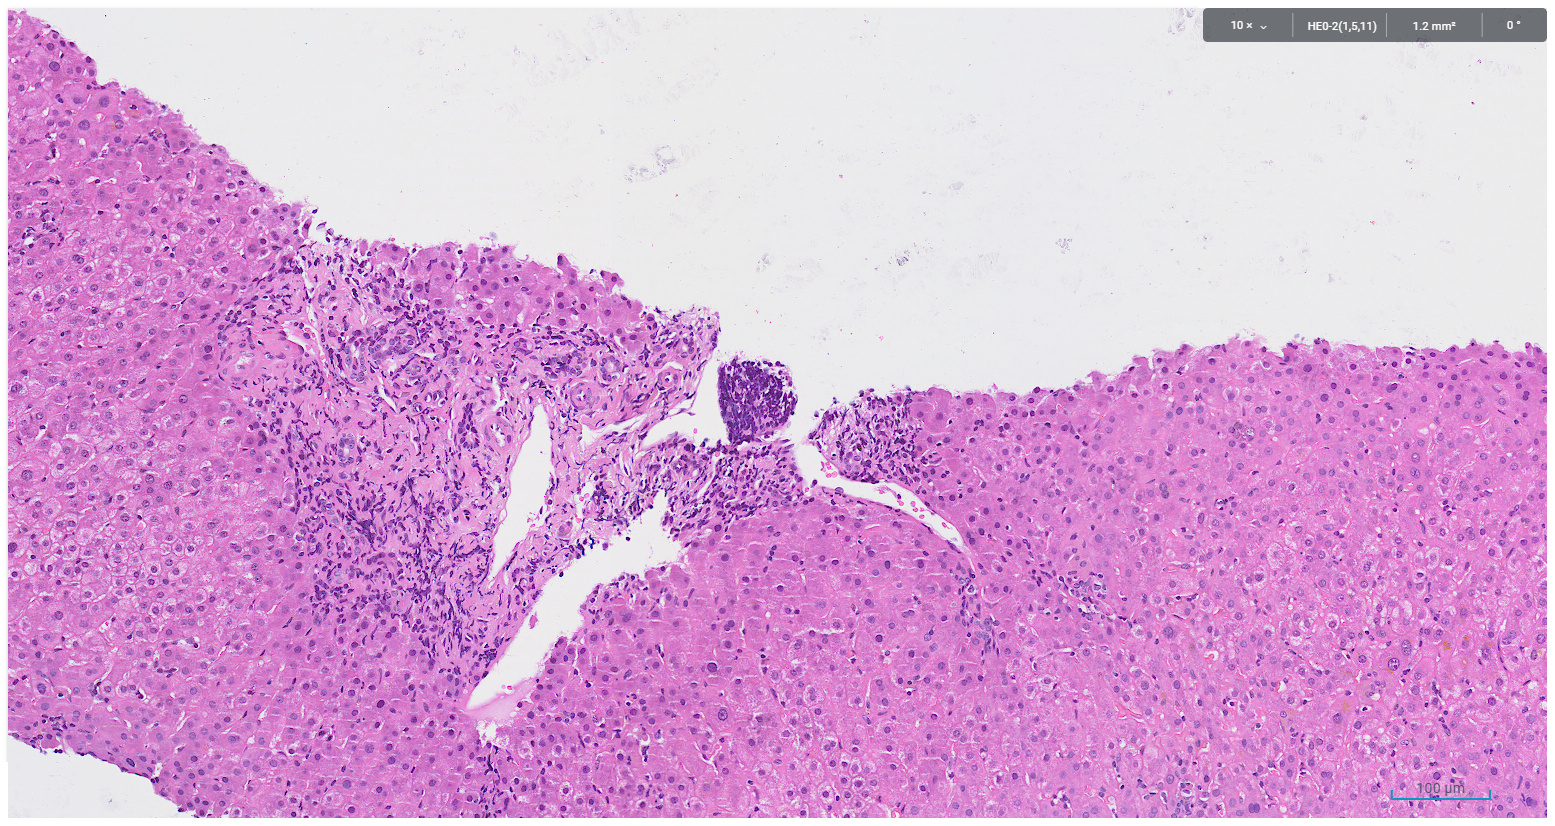

A core biopsy taken from the right hepatic lobe showed periportal chronic inflammation without a prominent plasma cell component, and focal interface activity (Figure 1). Mild bile ductular proliferation and mild periportal fibrosis were noted and highlighted with CK7 immunohistochemistry (Figures 2 and 3). There was no evidence of bile duct injury or ductopenia. The hepatic lobules contained scattered chronic inflammatory infiltrate and mild canalicular cholestasis (Figures 4 and 5). Steatosis, confluent necrosis, Mallory-Denk bodies and granulomata were not identified.

Figure 1. Periportal chronic inflammation devoid of plasma cells, with focal interface activity

Figure 2. Bile ductular reaction, periportal fibrosis and chronic inflammation devoid of plasma cell infiltrate